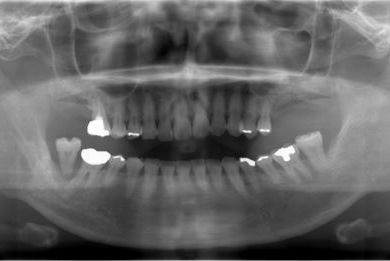

インプラントの症例写真 IMPLANT

骨再生インプラント治療+セラミック治療+歯肉歯槽骨整形

| 性別/年齢 | 女性 / 42歳 | ||||||||||||||||||||||||||||||||

| 主訴 | インプラント治療を受けたい。 | ||||||||||||||||||||||||||||||||

| 治療方針 | 左上奥欠損部分をインプラント治療にて機能的・審美的回復を行う。 | ||||||||||||||||||||||||||||||||

| 治療内容 | インプラント2本(ソケットリフト)、メタルボンドセラミック3本(メタルボンド用土台1本)、歯肉歯槽骨整形 | ||||||||||||||||||||||||||||||||

| 総治療費 | 1,227,713円 | ||||||||||||||||||||||||||||||||

| 治療期間 | 11ヶ月 |